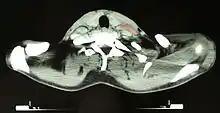

Hodgkin lymphoma

Hodgkin lymphoma- hilum overlay sign